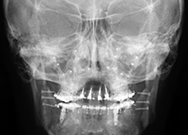

Telerradiografia Frontal

É um exame utilizado para análise das medidas frontais do crânio e da face, com o objetivo de identificar a simetria e harmonia na posição da maxila, mandíbula e do esqueleto facial. Para sua obtenção é necessário manter uma distância específica que propicie padronização nas imagens.